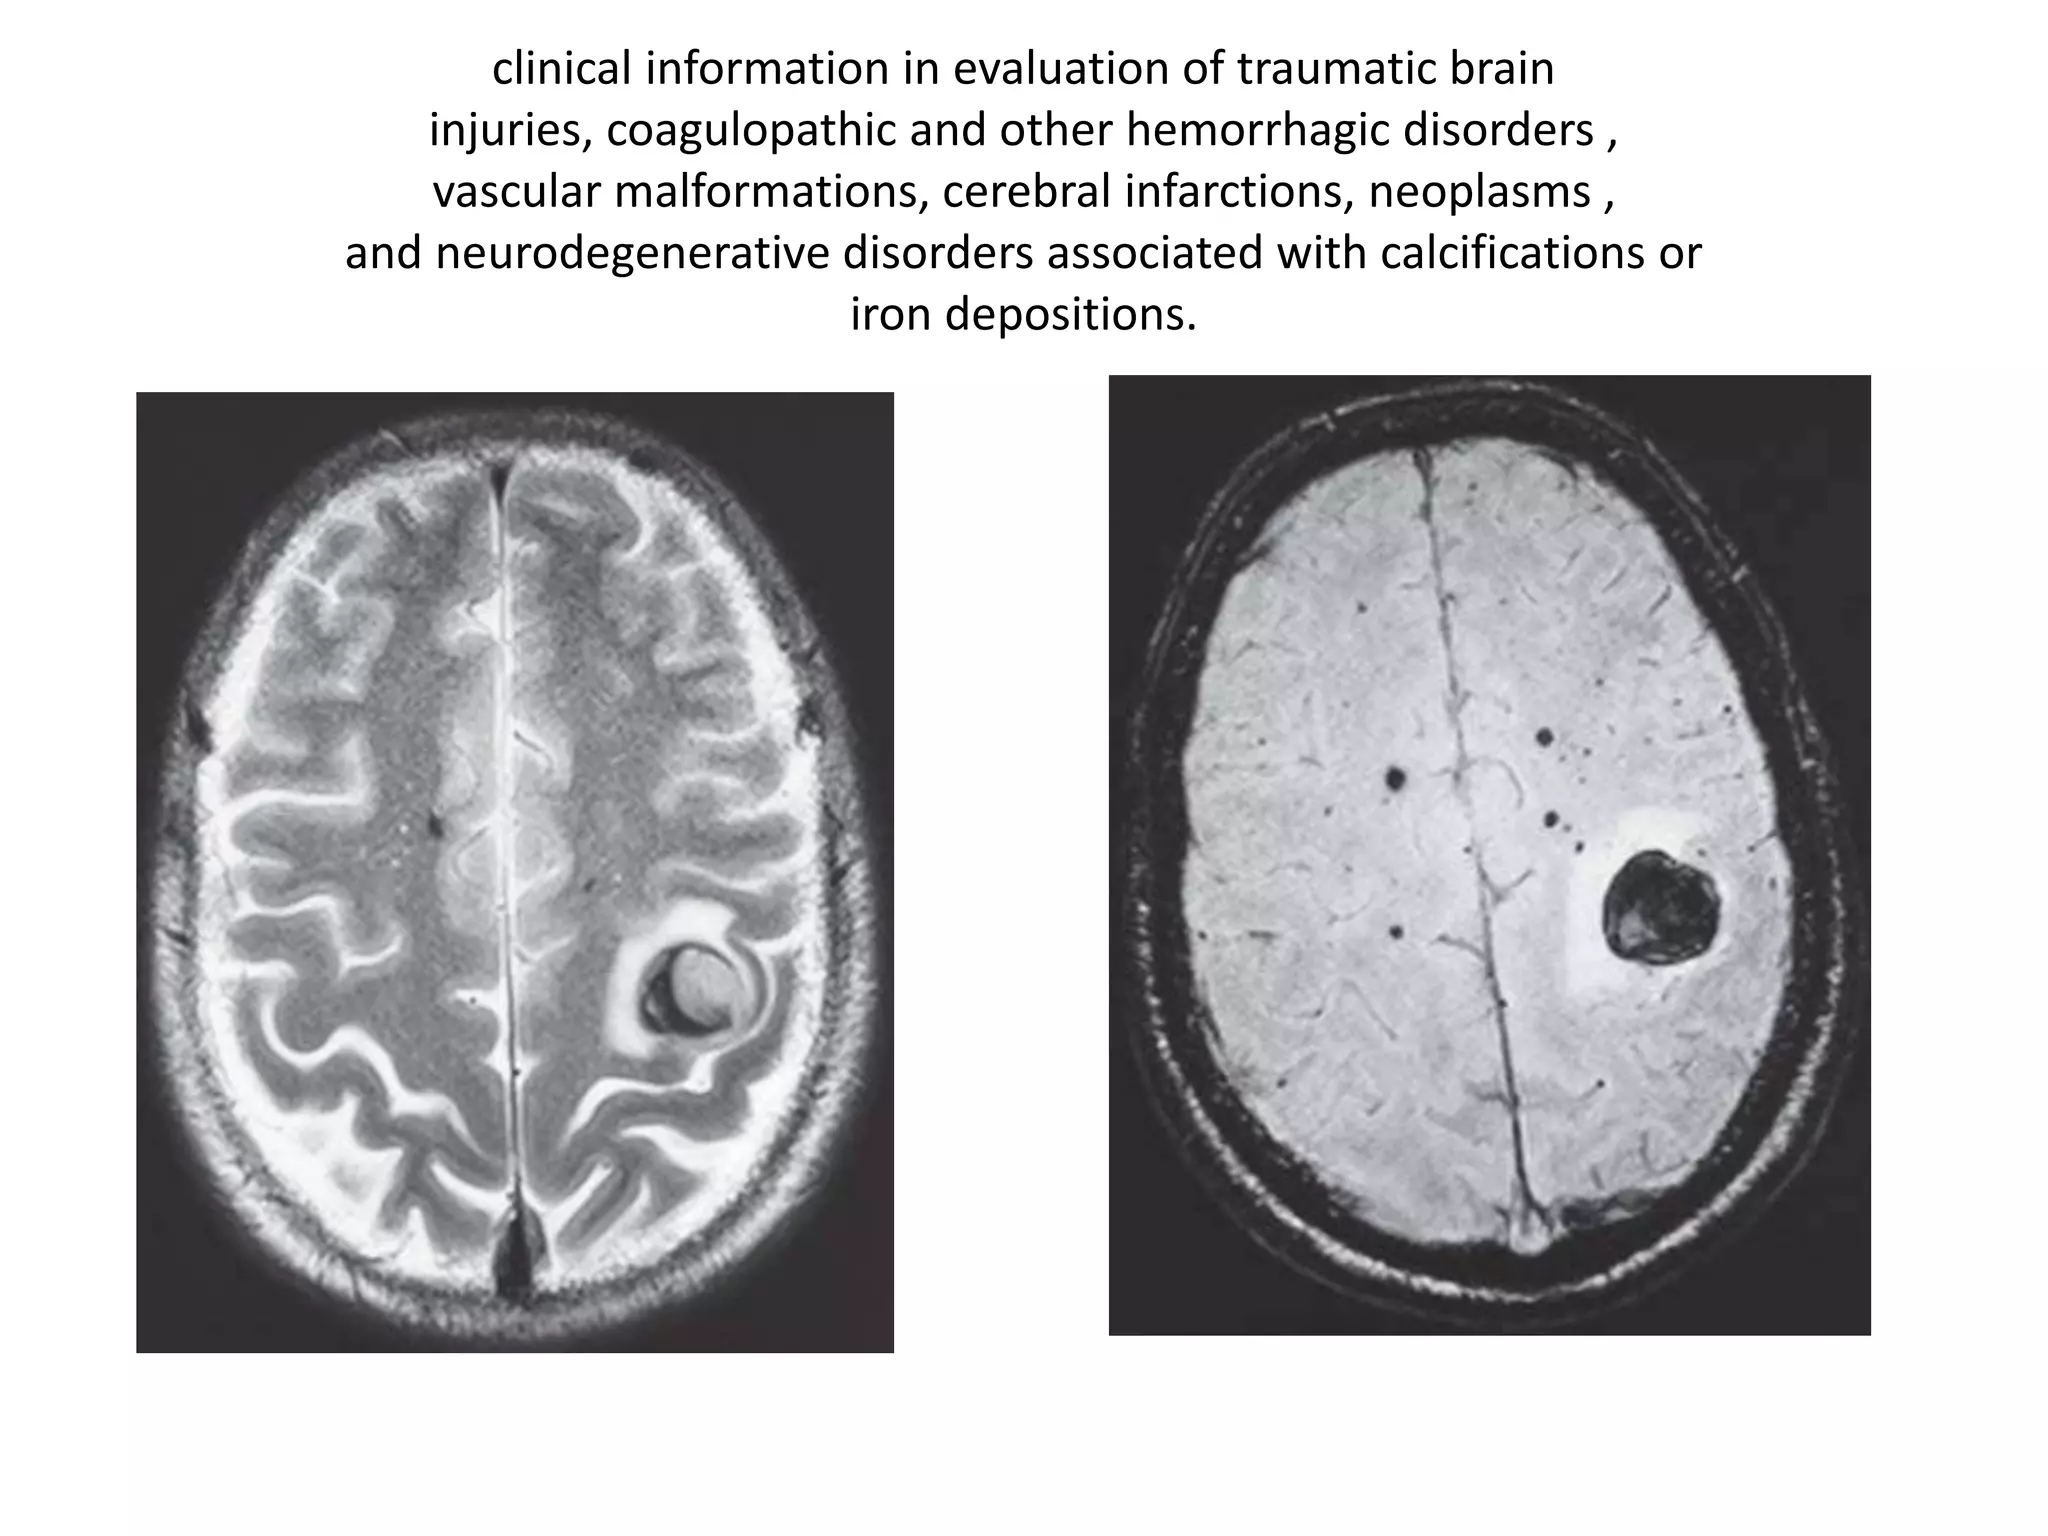

Susceptibility Weighted Imaging (SWI)

• tissues of higher susceptibility distort the

magnetic field and become out of phase

• Unlike initial experience with Spoiled GRE,

with advent of 3T and parallel imaging, it is

now possible to image the entire brain with

SWI in a short time.

clinical information in evaluation of traumatic brain

injuries, coagulopathic and other hemorrhagic disorders ,

vascular malformations, cerebral infarctions, neoplasms ,

and neurodegenerative disorders associated with calcifications or

iron depositions.